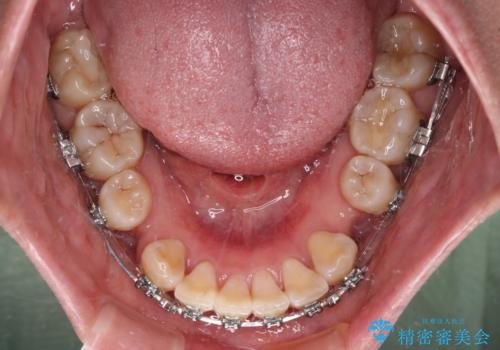

- メタルブラケット

- 2年6ヶ月

骨格的に上顎歯列が前方位にあり、口元の突出感が顕著な状態で、上下左右の第一小臼歯4本を抜歯して、ワイヤー装置での抜歯矯正を行うこととしました。

奥歯の咬み合わせ改善のために、アンカースクリューの使用と上顎左右第一小臼歯の抜歯のタイミングをコントロールして、理想的な咬み合わせに仕上げていくこととしました。